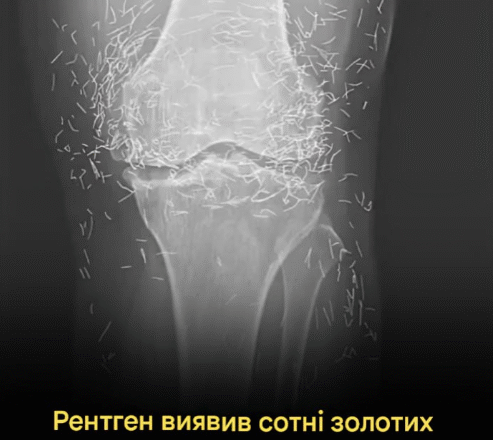

Коли лікарі досліджували рентгенівський знімок колін літньої жінки, яка страждала від сильного болю в суглобах, вони знайшли золоту жилу: сотні крихітних золотих голок для акупунктури, залишених у її тканинах.

У звіті йдеться, що під час лікування жінки акупунктурою голки, які, ймовірно, були виготовлені з золота, були навмисно залишені в її тканинах для подальшої стимуляції.

Це також може ускладнити для лікаря читання рентгенівського знімка. «Голки можуть приховувати деякі анатомічні органи», – сказав Гермазі.